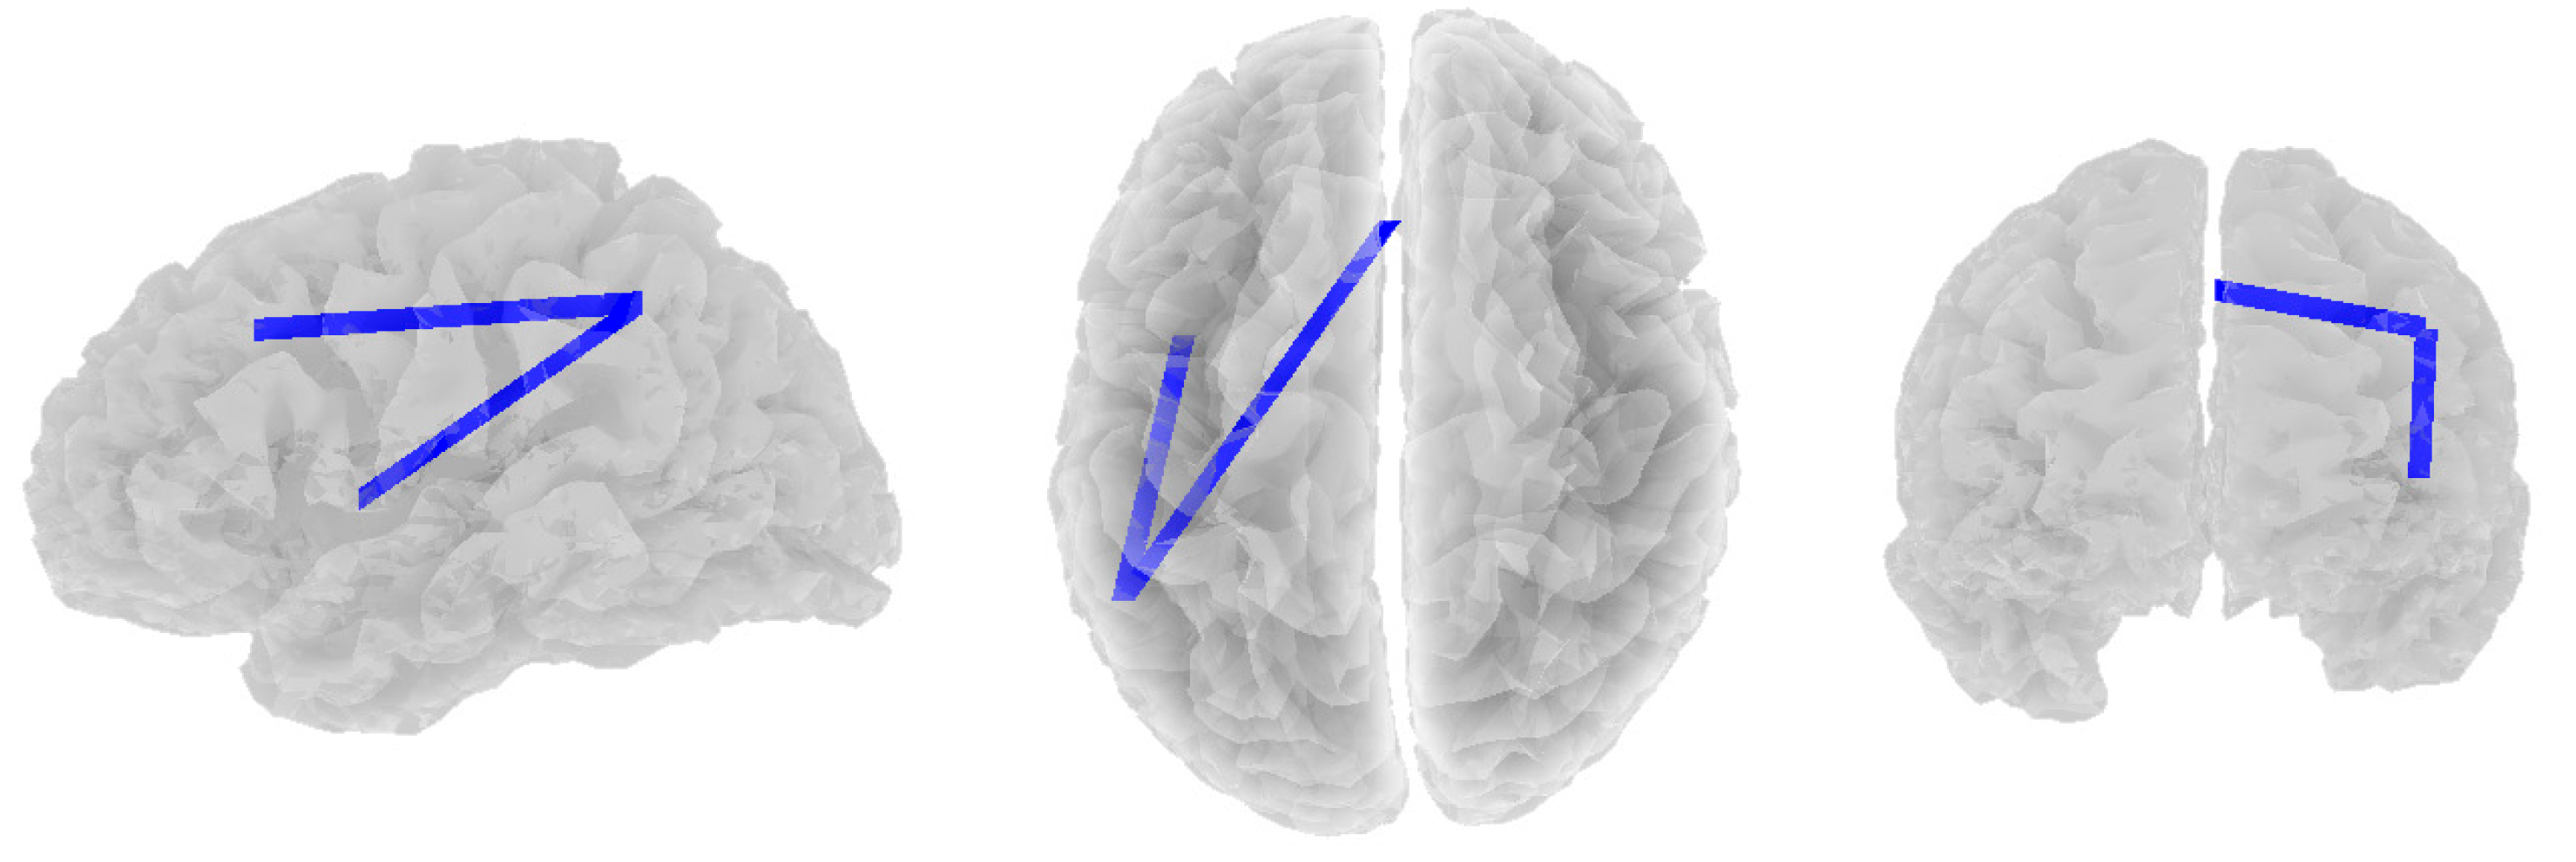

3.2. Alpha Band

3.3. Beta Band

3.4. Theta Band